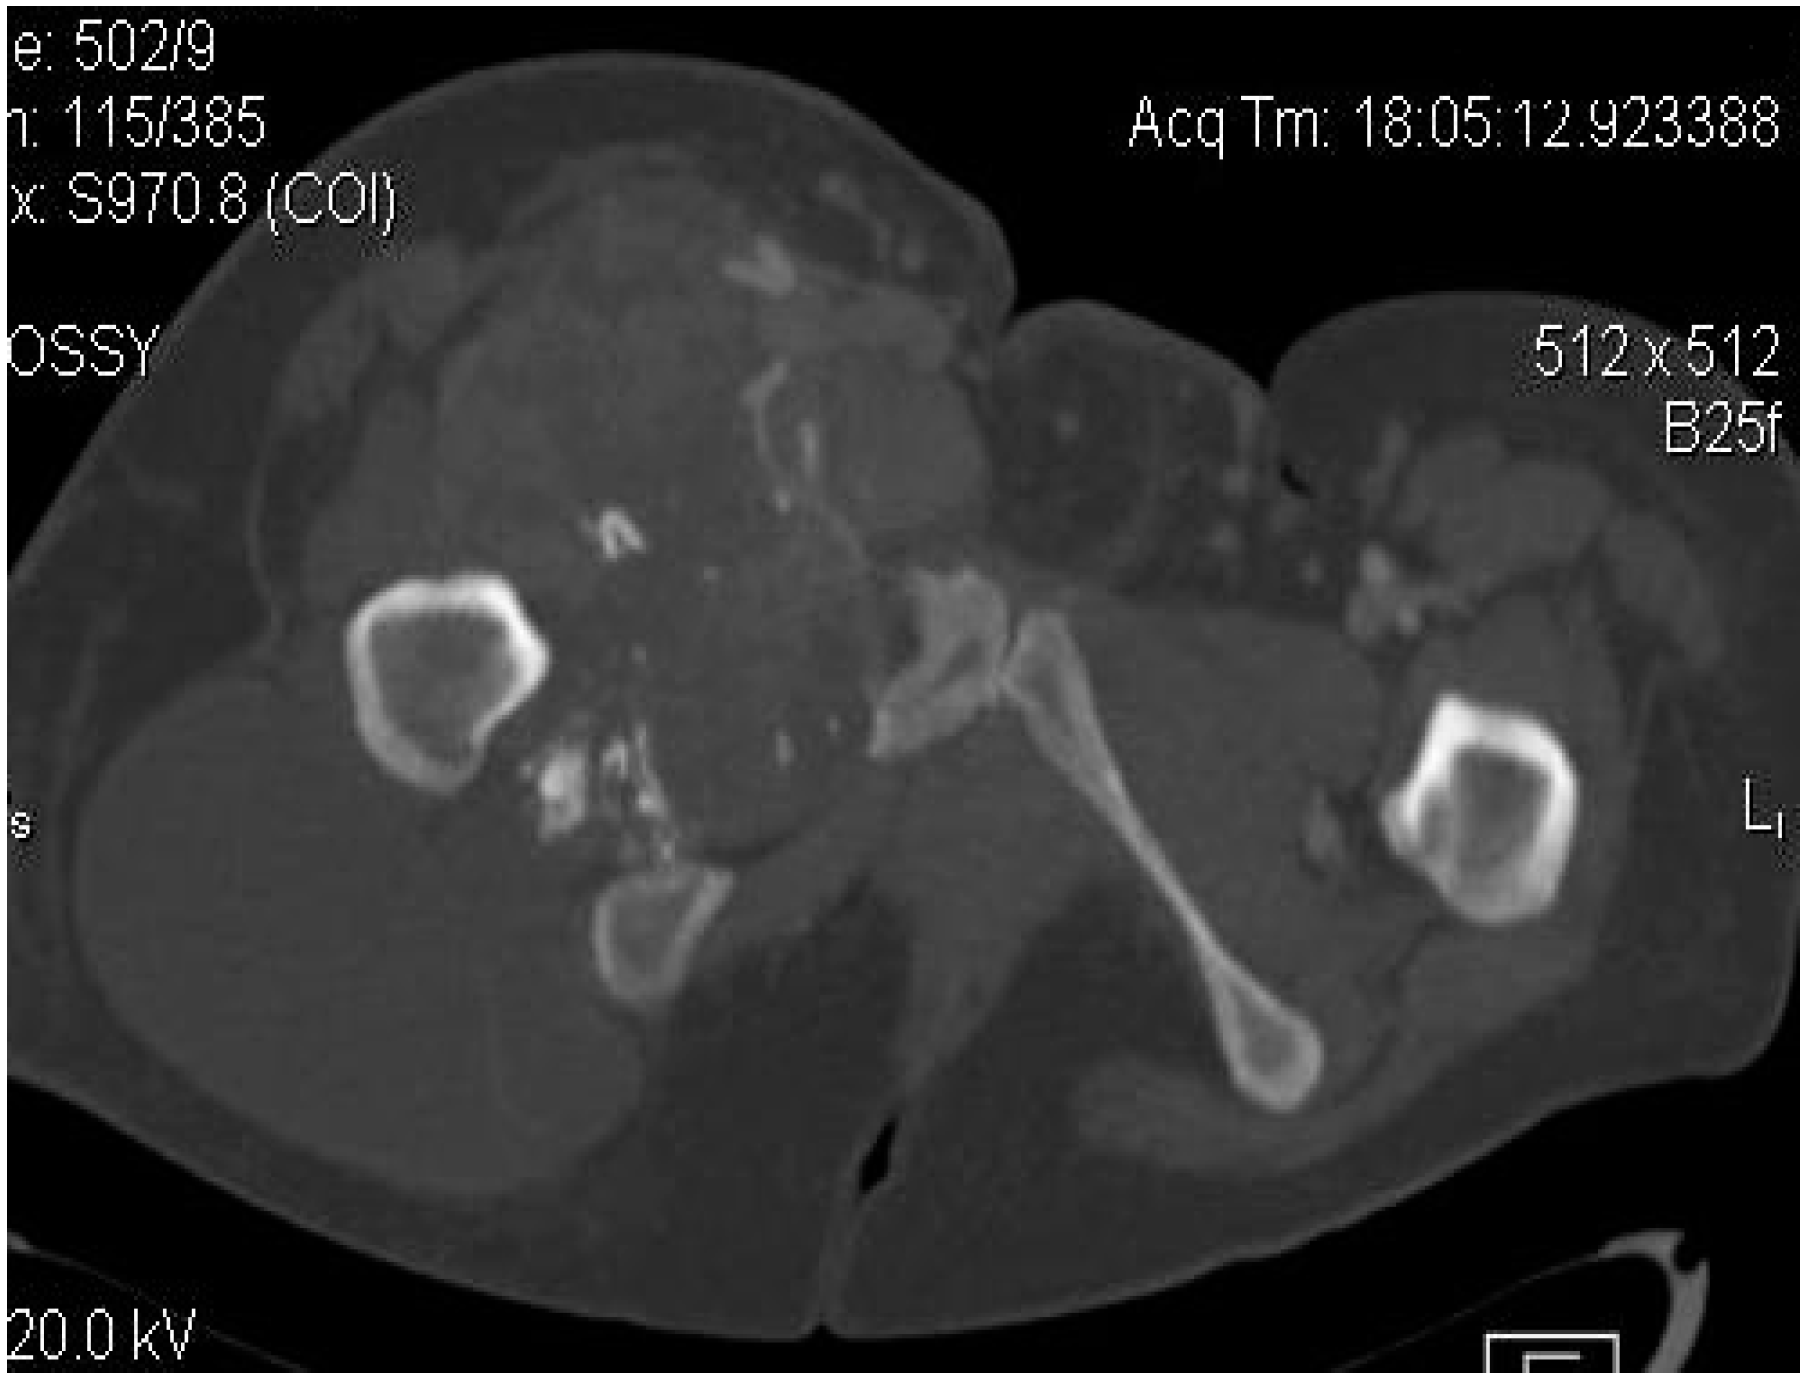

Computed tomography (CT) is usually performed either if the MRI is contraindicated (e.g., due to the presence of orthopedic implants), is unavailable or if the radiologists need additional information regarding the local bone involvement or better visualization of the intratumoral calcifications (Figure 4, Figure 5 and Figure 6).

Figure 5.

Synovial sarcoma, F, 31 YO patient—CT image, axial section: soft-tissue mass with heterogeneous content, showing necrotic areas alternating with calcifications and cystic areas.

Figure 6.

Synovial sarcoma, F, 31 YO patient, CT image, axial section, with contrast—bone window: osteolytic area in the right ischio-pubic rami.